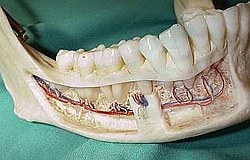

Der Zahn wird in seinem Zahnfach in mehrere kleine Teile zerlegt

Er dadurch muss man wenig Knochen abtragen

Nach der Naht heilt die Wunde schnell.